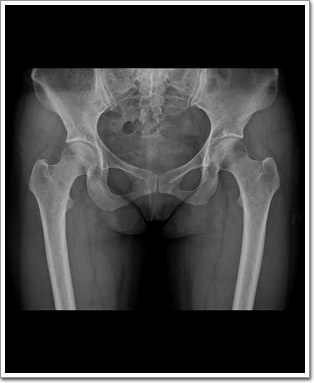

Hip AP

Femoral Head Femoral Neck Fracture여부, Greater Lesser TrochantersFracture 여부를 관찰 한다.

환자는 Supine Position을 취한다. Femoral Neck Anteversion을 방지하기 위해 양쪽 발을 벌린다음 발끝을 15°정도 안쪽으로 회전시킨다.

Greater trochanter는 명확히 나타나야 하고, lesser trochanter내측연에 나타내어져야 하며,  좌우 대칭이 되어 나타나야 한다.